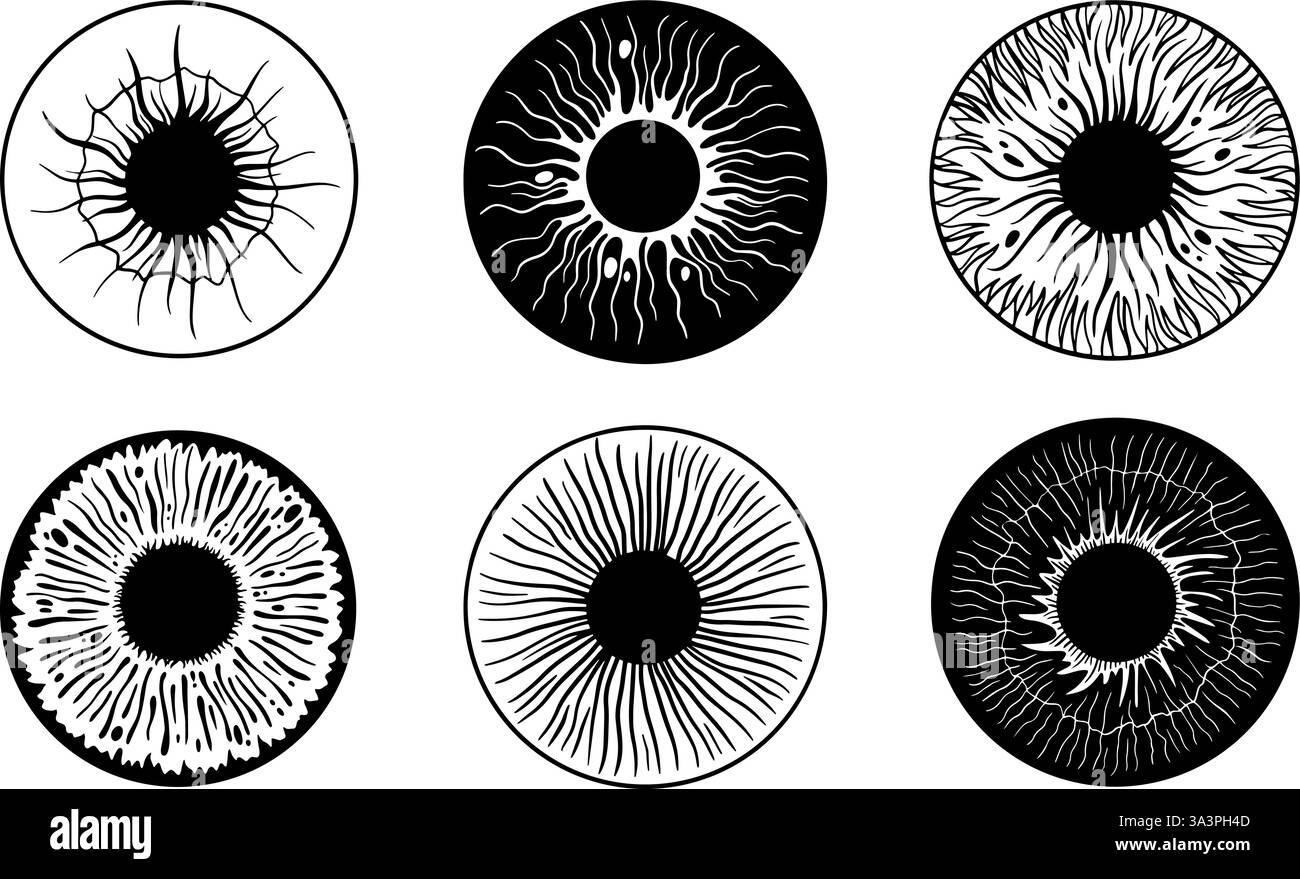

Structure de l'oeil humain. Iris éléments anatomiques, personne abstraite iris macro style. Contrôle de la vision, pupilles différentes, ophtalmologie vecteur néotérique Illustration de Vecteurhttps://www.alamyimages.fr/image-license-details/?v=1https://www.alamyimages.fr/structure-de-l-oeil-humain-iris-elements-anatomiques-personne-abstraite-iris-macro-style-controle-de-la-vision-pupilles-differentes-ophtalmologie-vecteur-neoterique-image656334349.html

Structure de l'oeil humain. Iris éléments anatomiques, personne abstraite iris macro style. Contrôle de la vision, pupilles différentes, ophtalmologie vecteur néotérique Illustration de Vecteurhttps://www.alamyimages.fr/image-license-details/?v=1https://www.alamyimages.fr/structure-de-l-oeil-humain-iris-elements-anatomiques-personne-abstraite-iris-macro-style-controle-de-la-vision-pupilles-differentes-ophtalmologie-vecteur-neoterique-image656334349.htmlRF3A3PH4D–Structure de l'oeil humain. Iris éléments anatomiques, personne abstraite iris macro style. Contrôle de la vision, pupilles différentes, ophtalmologie vecteur néotérique